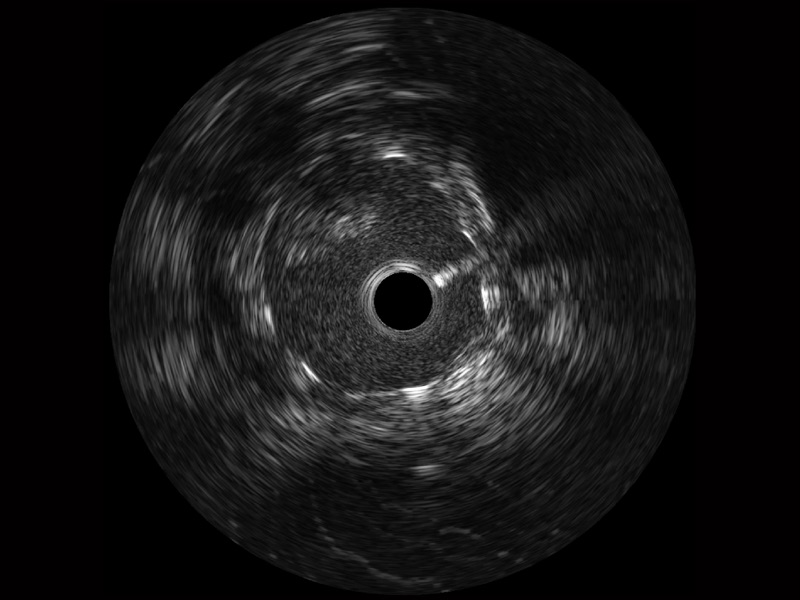

開立寬頻IVUS圖像

對比傳統(tǒng)IVUS導(dǎo)管成像,開立寬頻IVUS圖像的近場支架梁顯影更細(xì)膩,遠(yuǎn)場中膜外血管仍清晰可辨,兼顧遠(yuǎn)中近,兼顧分辨力與穿透深度